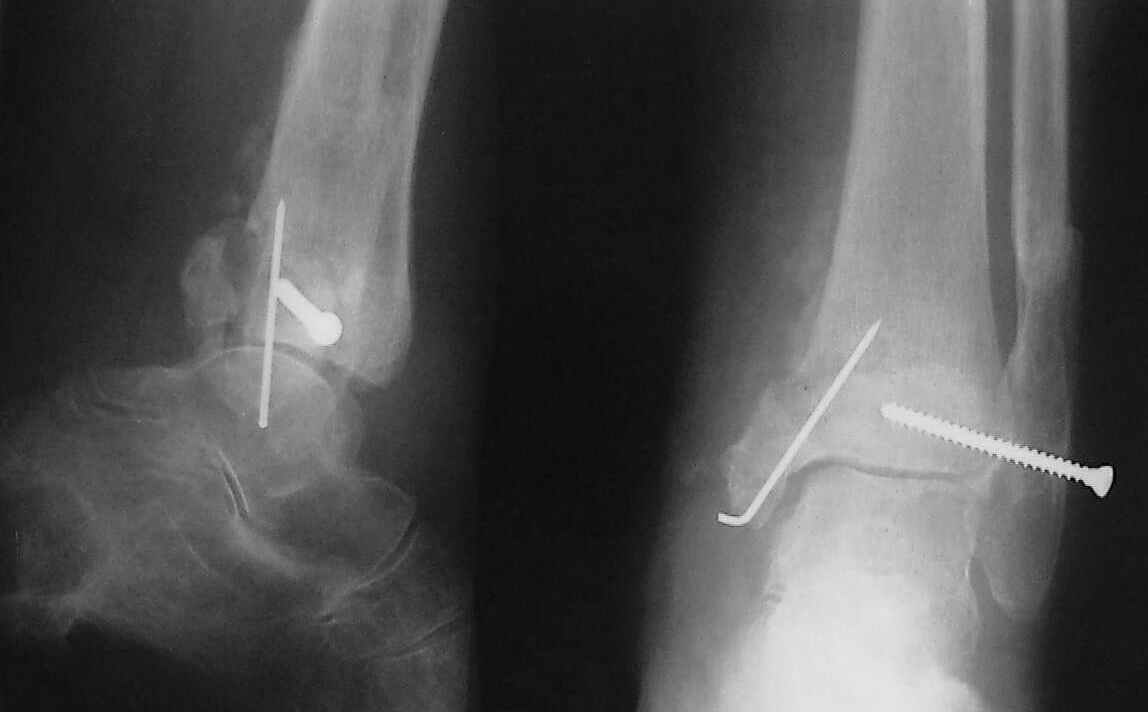

Больная 1936 г.,травма 15 ноября 2003,закрытый трехлодыжечный перелом г/стопного сустава, сахарный диабет.

При поступлении - закрытая репозиция, повторная в связи с большим отеком через неделю, подготовлена к остеосинтезу в первых числах декабря. Заживление без осложнений. Циркулярный гипс - 7 недель, снят,часть спиц удалено 20 февраля т.к.пальпировались под кожей, постепенная нагрузка, проблем нет до середины апреля когда появильсь боли с мед. стороны сустава и локалная гиперемия ( трактовалась как флеботромбоз). Повторное поступление 15 апреля - усиление болей,пов. температура, локально выраженная гиперемия.Локально выделений нет. На RTG - деструкция в области мед лодыжки и заднего края. Сахар крови умеренно повышен. Как трактовать проблему, какой диагноз и тактика лечения? Заранее спасибо, Владимир.

Я бы проблему трактовал как изначально нестабильный и нефункциональный остеосинтез с длительной иммобилизацией у больной с сахарным диабетом, ангиопатией и остеопорозом.

Диагноз я бы поставил: неправильно срастающийся перелом обеих лодыжек и заднего края ББК. Ложный сустав мед. лодыжки? Хронический вялотекущий остеоимиелит голеностопа. Сопутствующий - СД, диабетическая ангиопатия 2.

А почему изначально не сделали хоть по Веберу? В чём смысл 6-ти скусанных спиц? И для чего ввинтили несоответствующий методике шуруп в нижнюю треть остеопорозной, практически отсутствующей лодыжки?

Ретроспективно, на Ваш взгляд, что изменилось бы при остеосинтезе более массивными имплантами?(выбор в пользу спиц как раз и был из-за минимального объема оставляемых имплантов) Иммобилизация 7 недель это очень длительно? Результат на 4 RTG - в чем нефункциональность? - согласен, что репозиция заднего края не была достигнута. Какие признаки ложного сустава мед. лодыжки ?

Уважаемый Владимир. Нестабильность и нефункциональность, как мне видится по снимочкам, была изначально,об этом ниже В чём вы видите массивность третьтрубчатой, например титановой 1.5 мм пластины? Ими оперируют во всём мире и получают хорошие результаты, а почему у нас это массивно мне непонятно.Спицевая "тюрьма" хороший способ, но только для временной интраоперационной фиксации, хотя лично я редко пользуюсь, на то есть костодержатели для малых фрагментов и репонирующие винты. Кстати в данном случае, при её остеопорозе лучше было бы поставить LCP (опуская финансовую сторону вопроса, в теории). А вот функциональность - при правильном подборе и установке металлоконструкций пациент нуждается в иммобилизации на срок заживления швов, а уж потом ходьба без нагрузки на оперированную конечность 6 недель - (базовый курс АО). Ретроспективно, как мне видится, при хорошей репозиции и фиксации всё бы консолидировалось, хотя на всё воля божья, но по крайней мере не нужно было бы удалять железки. Иногда ставишь всё как мама родила, а потом очень плохие последствия. Признаки ложного (?) я вижу на снимках,хотя это может быть и банальное отсутствие консолидации за столь длительный срок, что само по себе я бы расценил как ложный сустав. А что Вы сами думаете по этому поводу? И как планируете артродезировать? (если планируете). Мне кажется, самое обидное то, что и эндопротез голеностопного поставить там просто некуда. Я бы думал об очень сомнительном прогнозе.